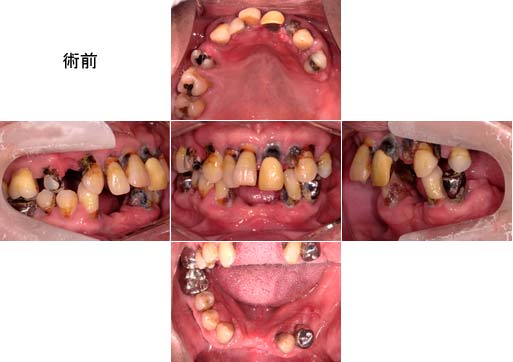

両奥歯が崩壊し、前歯の脱離が起きやすく噛みにくいということで来院されました。

歯周再生治療と、審美補綴治療によってトータルコーディネートをしました。

治療後は、「見た目も綺麗で、噛みやすくなった」と満足されています。 |